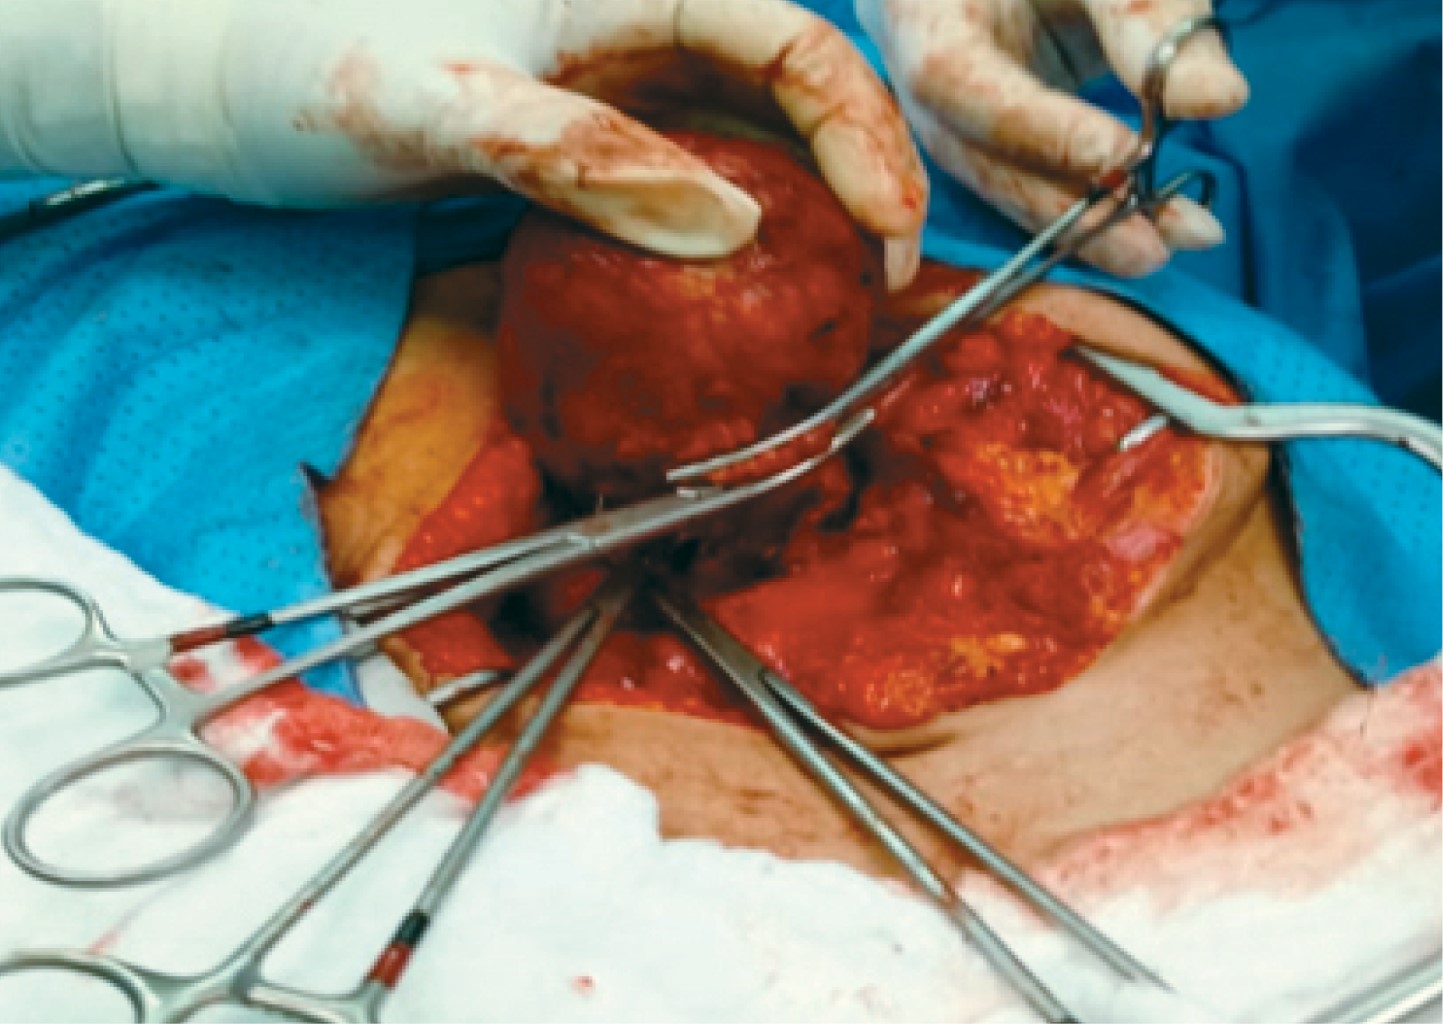

The patient underwent exploratory laparotomy where a tumor mass of approximately 6 × 8 cm was identified at the level of the head of the pancreas attached to the second portion of the duodenum, so we proceeded to perform enucleation by dissection of the second portion of the duodenum and the trans-pancreatic portion involving the main pancreatic duct, The duodenum was then splinted with a No. 12 Nelaton, which was exteriorized through the second portion of the duodenum towards the abdominal wall at the height of the right flank, and fixed with a PDX 3 (polydioxanone) suture (Figures 2, 3 and 4).

Macroscopically the tumors are spheroidal or elliptical in appearance, well circumscribed, composed of a capsule with hemorrhagic and necrotic areas inside in 50% of the cases. The presence of calcifications and very friable septa is observed less frequently.4,5,7 The macroscopic form of our case was cystic, measuring 8 × 4.5 × 3 cm with a smooth pink-reddish surface due to bloody material and degenerative tissue.

The treatment of choice is surgical resection. Depending on the location, pancreatoduodenectomy should be performed if the lesion is at the level of the head and neck with duodenal involvement. Enucleation if there is trans-pancreatic involvement and central location, or distal pancreatectomy with splenectomy if the tumor is in the tail should be done. Surgical treatment presents low mortality and low recurrence rates.1,2,6 In our case, enucleation of the tumor mass with splinting of the duct of Wirsung was decided to perform to ensure the functionality after surgery.